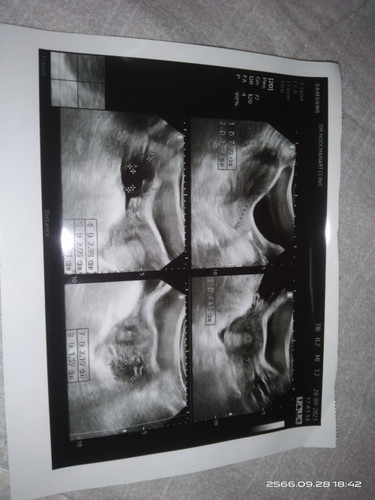

ไปหาหมอมา9wอัลตร้าซาวด์ว่ายังไม่พบถุงตั้งครรภ์แต่พบก้อนเล้กๆๆข้างขวา หมอนัดอีกทีวันที่9จะพอมีหวังไหม ใครเป็นแบบนี้ไหม อยากท้องมาก ดูให้หน่อย

อันนี้เป็นภาพอัลตราซาวด์9wค่ะ จะเห็นเป็นรูปร่างเริ่มมีเเขนออกเเล้วค่ะ เเต่ไข่อาจจะตกช้า ลุ้นไปด้วยนะคะ